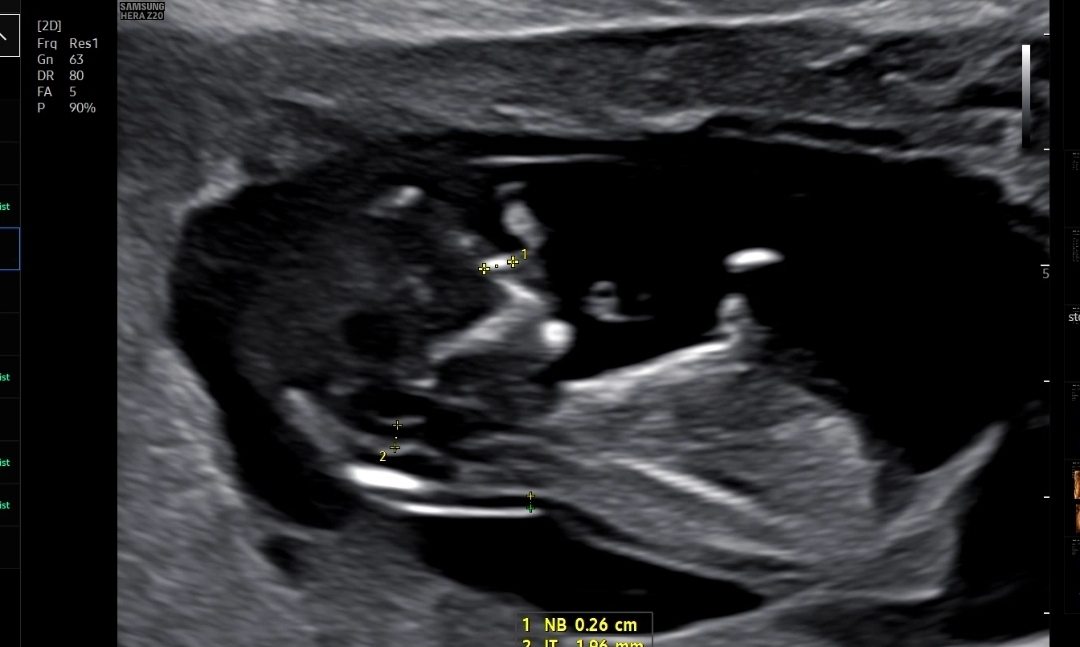

마지막으로 확인한 콧대길이, 소뇌?길이, 목투명대 길이를 쟀다

처음에 계속 뒤돌아 있어서 기침하고 했는데 약 10분간 애쓰다가 겨우 보여준 콧대

코뼈길이는 0.26cm, 목투명대는 1.31mm 로 둘다 정상범위!

만약에 코뼈가 낮거나 목투명대가 3mm이상이면 다운증후군 위험이 있다고 했다